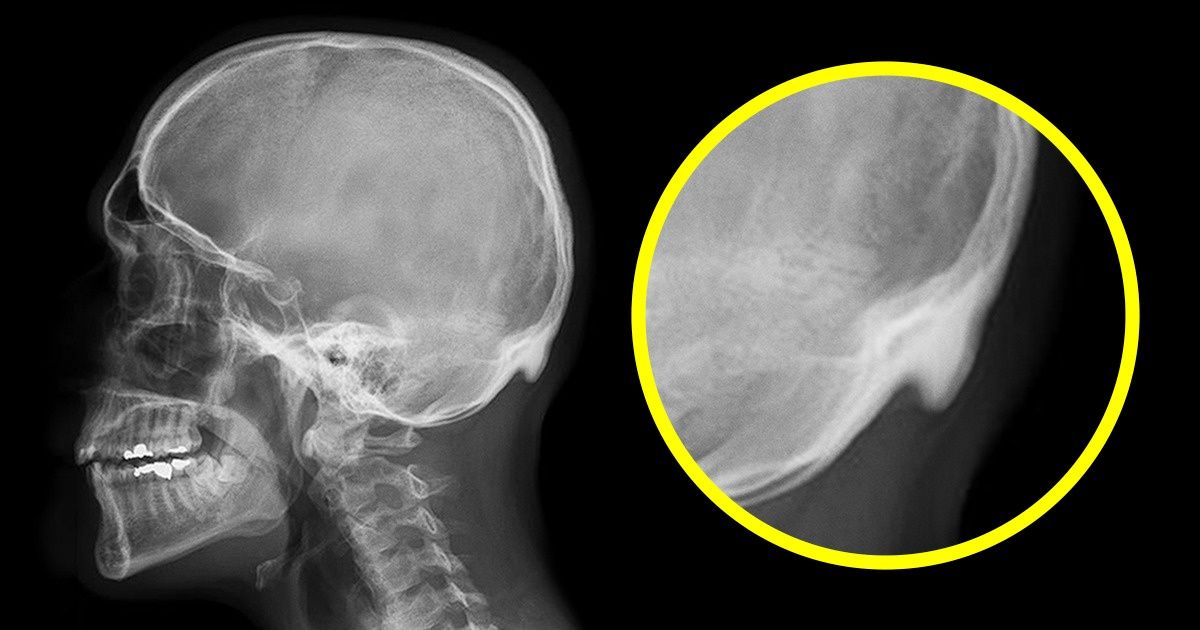

В исследовании приняло участие 218 человек в возрасте от 18 до 30 лет. У 41 % из них на рентгеновских снимках доктор Дэвид Шахар обнаружил костяной отросток на затылке. Притом что увеличенным считать этот нарост было решено начиная с 10 мм, у 10 % всех участников необъяснимый бугор выступал более чем на 20 мм, а максимальная его длина составляла целых 35,7 мм у мужчин и 25,5 мм — у женщин.

В ходе второго исследования ученые привлекли к эксперименту 1 200 человек в возрасте от 18 до 86 лет. Его результаты показали, что отросток чаще встречается у молодых людей. Поэтому доктор Шахар и его коллега Марк Сейер выдвинули гипотезу, что такое повреждение костей образуется из-за неправильной осанки. Из-за неестественного наклона вперед вес головы распределяется иначе и создается давление на место крепления мышц к черепу. В связи с этим происходят изменения в костях и сухожилиях. Сам нарост, по словам ученых, опасности не представляет, главной проблемой является искривленный позвоночник, который может спровоцировать другие нарушения в организме.